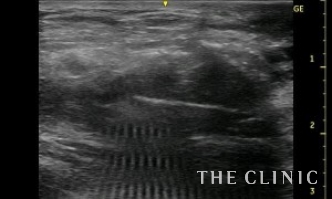

これをエコー下に穿刺吸引しました。